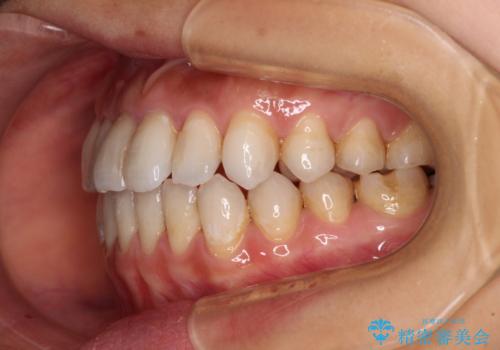

【モニター】開咬を治したい インビザラインによる矯正治療

- 上下前歯の開咬とデコボコを気にして来院された患者様です。

開咬(オープンバイト)はインビザラインによる矯正治療がワイヤー装置と比べて圧倒的に有利であるため、インビザラインによる矯正治療を行うこととしました。

通院されなかった時期があって治療期間が長くなったり、奥歯に抜歯が必要な歯があったりと、治療は一筋縄にはいきませんでしたが、何とか治療を終えることができました。